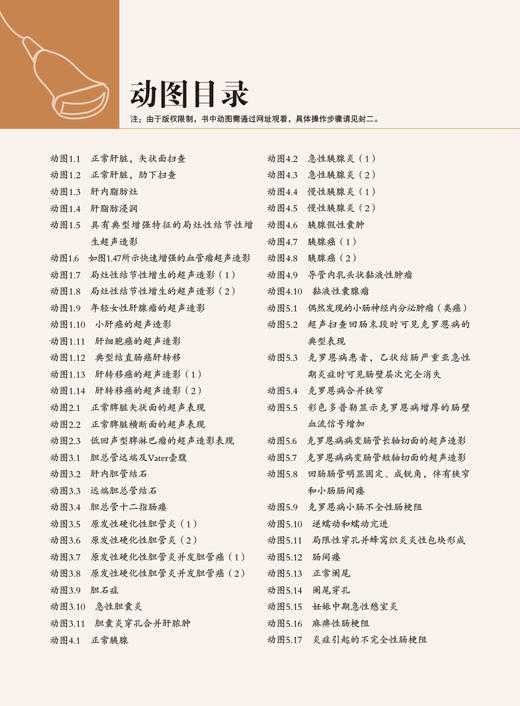

超声诊断学 第5版 消化系统分册 梁萍等译 肝脏脾脏胰腺胆道系统等脏器检查 超声影像诊断技术 基本技能规范 科学技术文献出版社